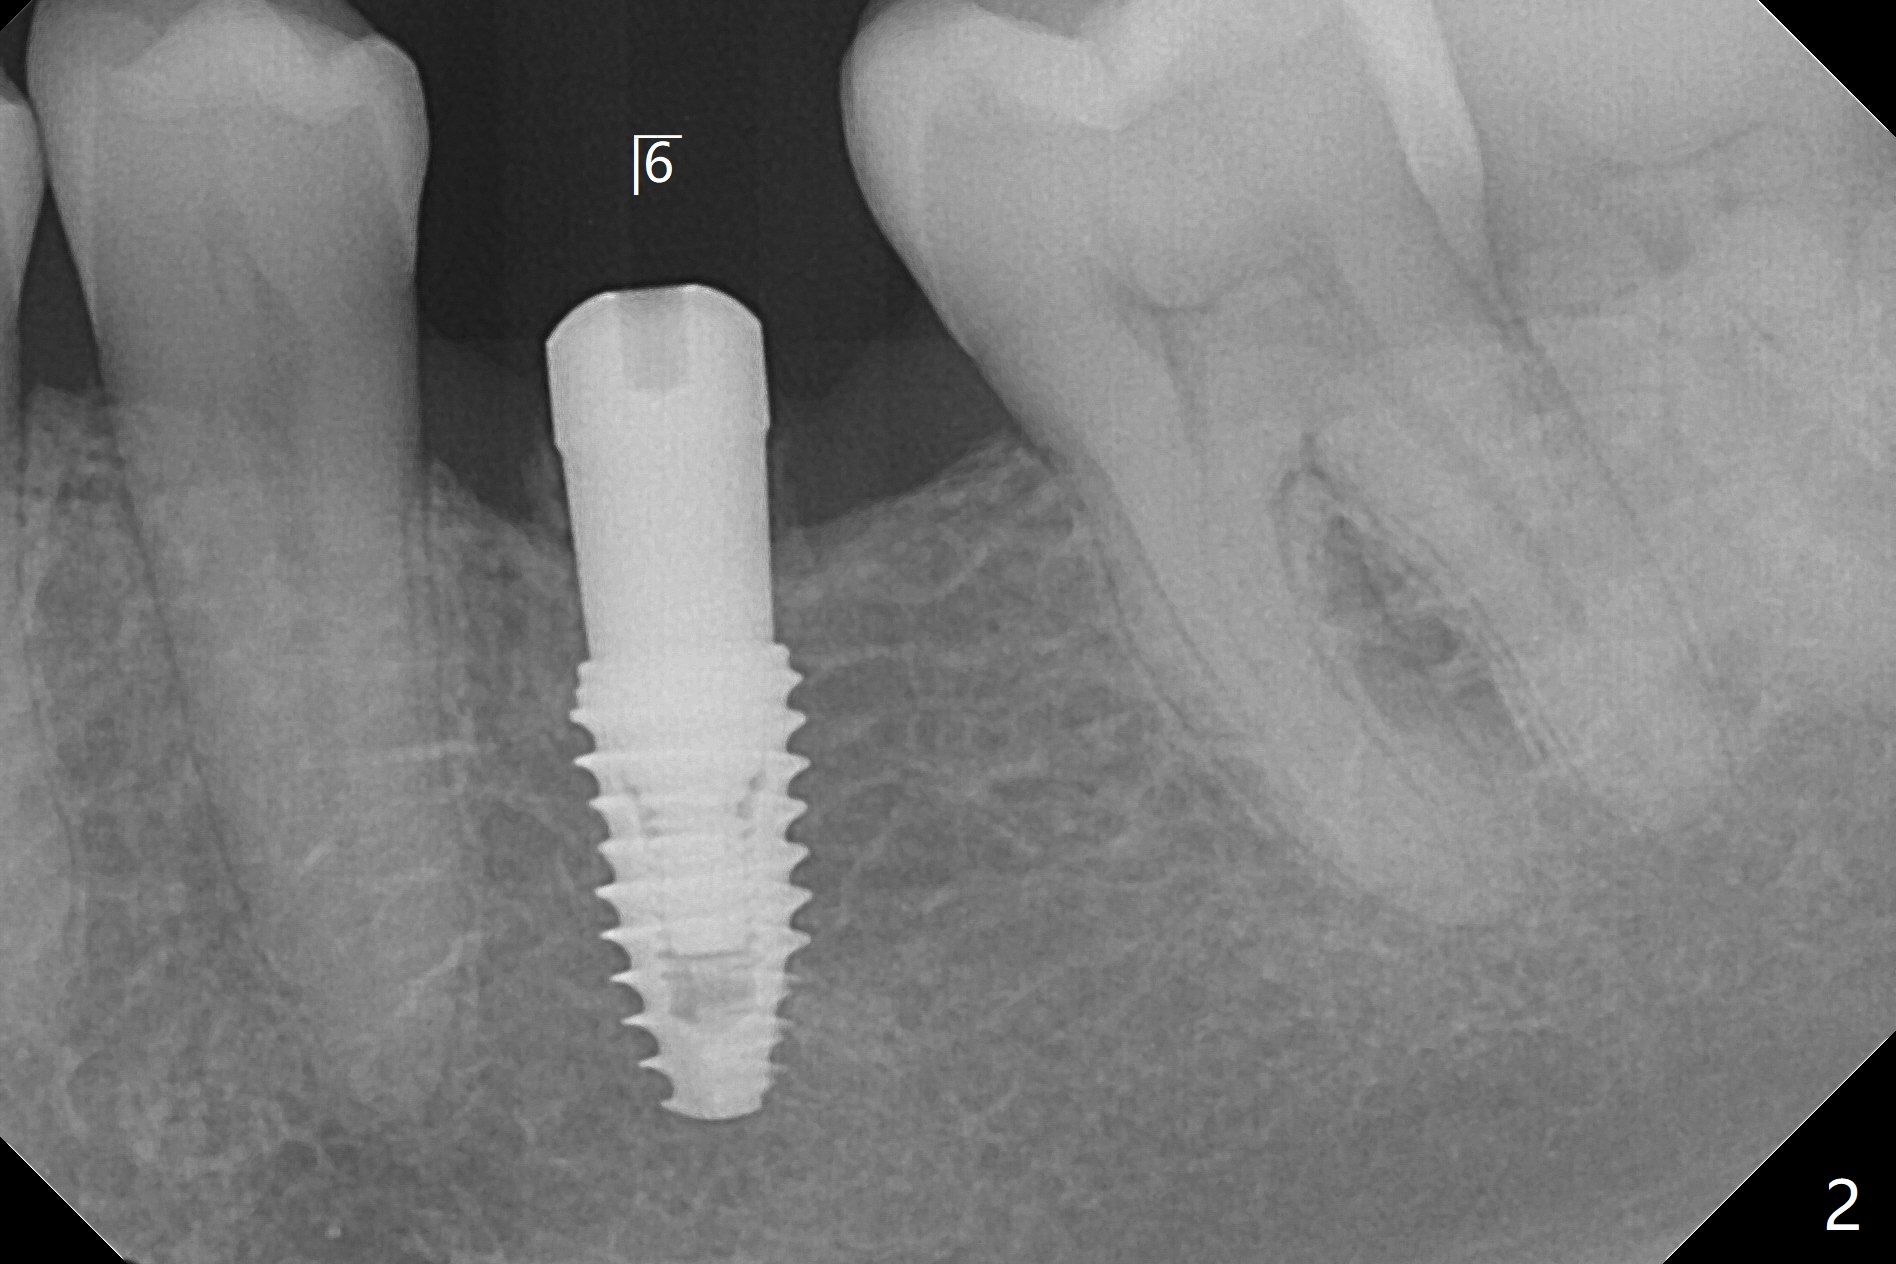

今天左下(图一,二),右下(图三)六种植,后者角化龈窄,事先做切口。两侧颊侧骨板均低,放置愈合基台后,在左下六基台和颊侧牙龈之间塞入骨粉(箭头),有点困难,应该事先做分离。而右下植骨在直视下进行,比较容易。

左下植体4毫米,放置4.5毫米愈合基台,不能就位,最后放置4毫米基台,完全入位(图一,二)。右下植体植入后,使用6毫米profile钻头,放置4.5毫米基台没问题(图三)。